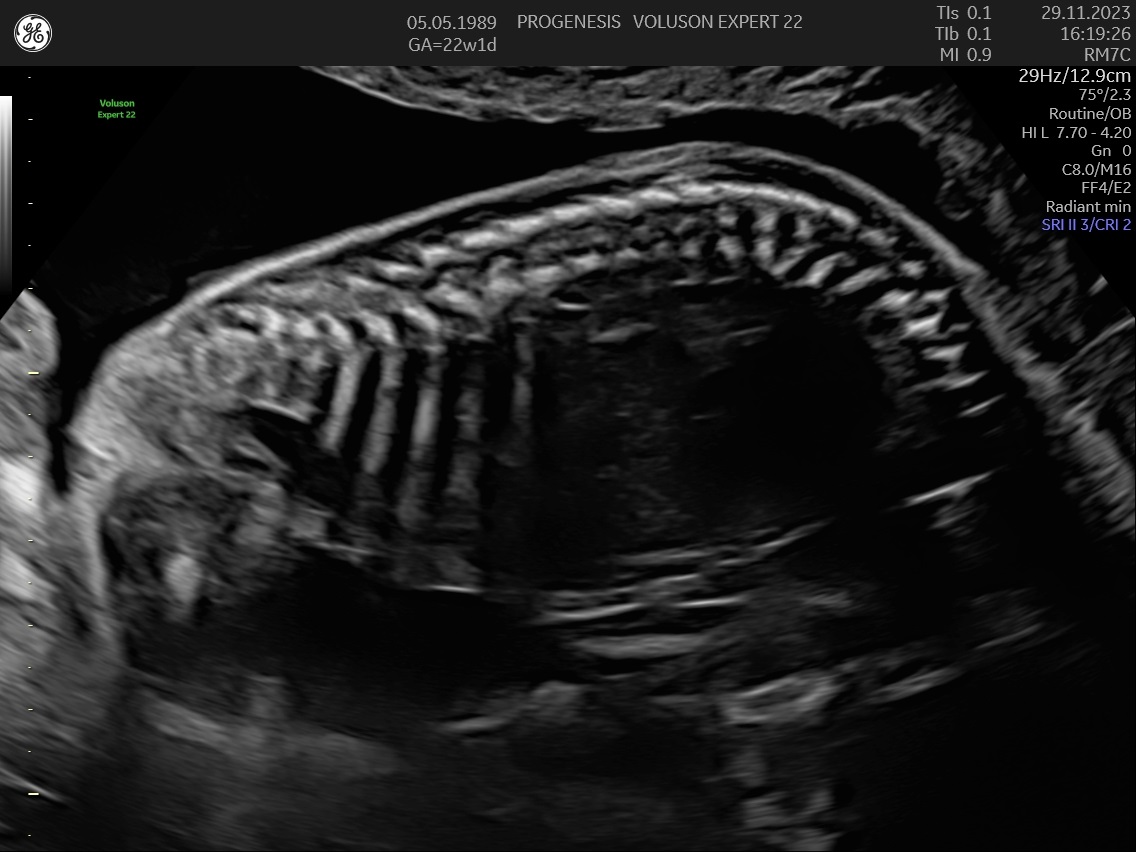

α) Η λεπτομερής αξιολόγηση της εμβρυϊκής ανατομίας, όπου αναγνωρίζονται τυχόν ανατομικές ανωμαλίες.

γ) Ο έλεγχος της ανάπτυξης του εμβρύου, του πλακούντα, του ομφαλίου λώρου και του αμνιακού υγρού.